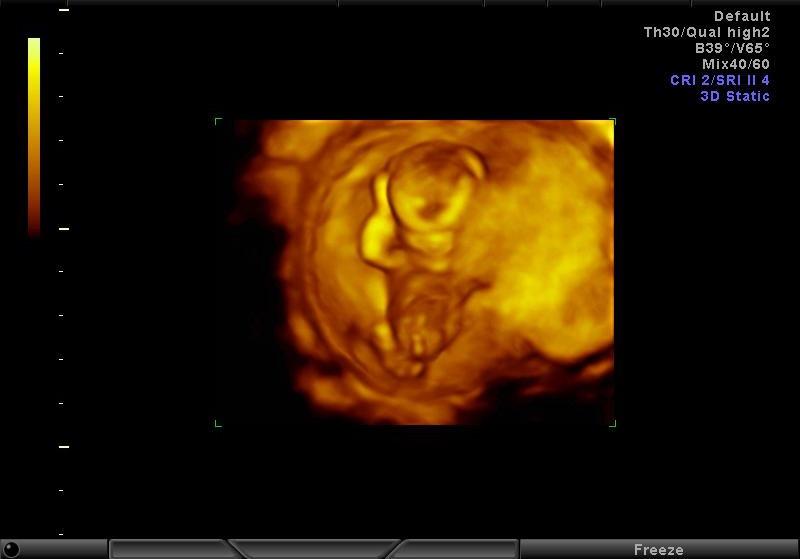

Tak baby,dnes 3D ultrazvuk... drobec sa dokonale skryval, bol pokrceny, nechcel sa vyrovnat... musela som ist pochodit, kaslat, lekarka mi buchala ultrazvukom po brusku ale on nas mal na haku 😁 Potom bol pretoceny dole hlavou... nechcel sa fotit... akurat mi dr nasla dost velky hematom,takze sa musim objednat na hematologiu. Mali ste to niektora?? 😳

@milasik10 bože to je nádherne ako na obláčiku 👶😘

@butterfly333 mam aj viac foto ale ta je najkrajsia... teba tichucko sledujem a drzim Ti veeeeelmi palce, nech ta MS obchadza 😉😉😉👍